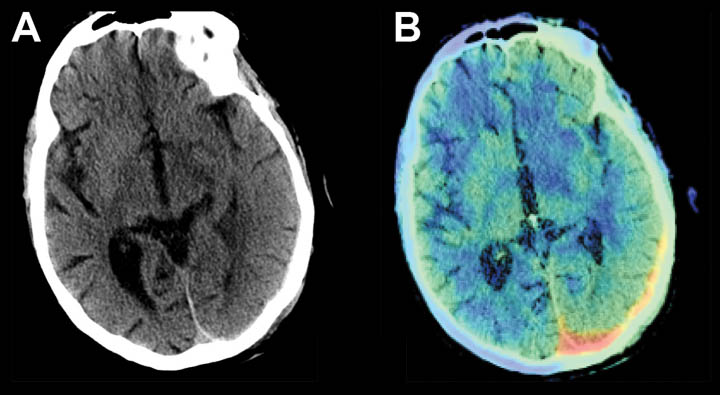

- Subtle, isointense, left subdural hemorrhage on head CT.

- AI based software highlights the area of hemorrhage, color coded in red.